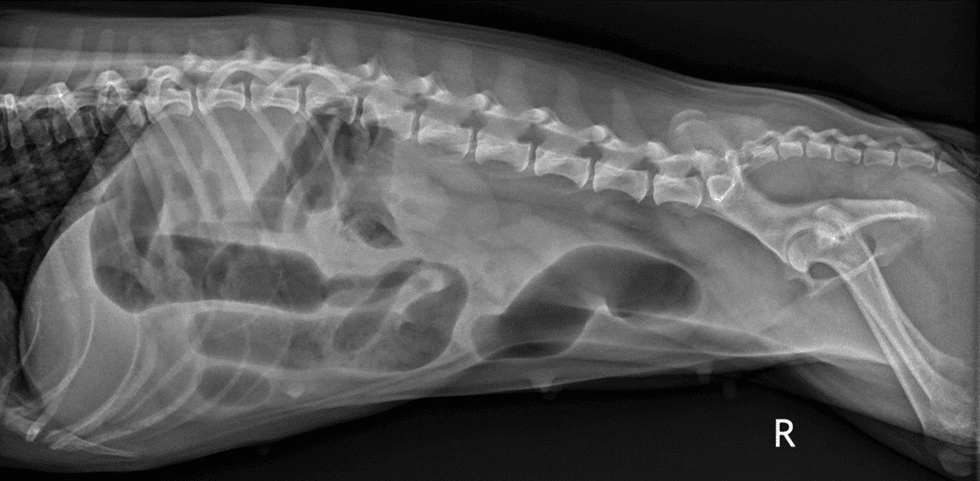

Dr. Hohenhaus says signs of an obstruction, either from a hairball or something else, include decreased fecal output as well as a lot of vomiting, including immediately after eating. If an animal doesn't want to eat, that's another red flag, including if decrease appetite is accompanied by continued vomiting. Such symptoms require x-rays to check for a blockage (see photo below).